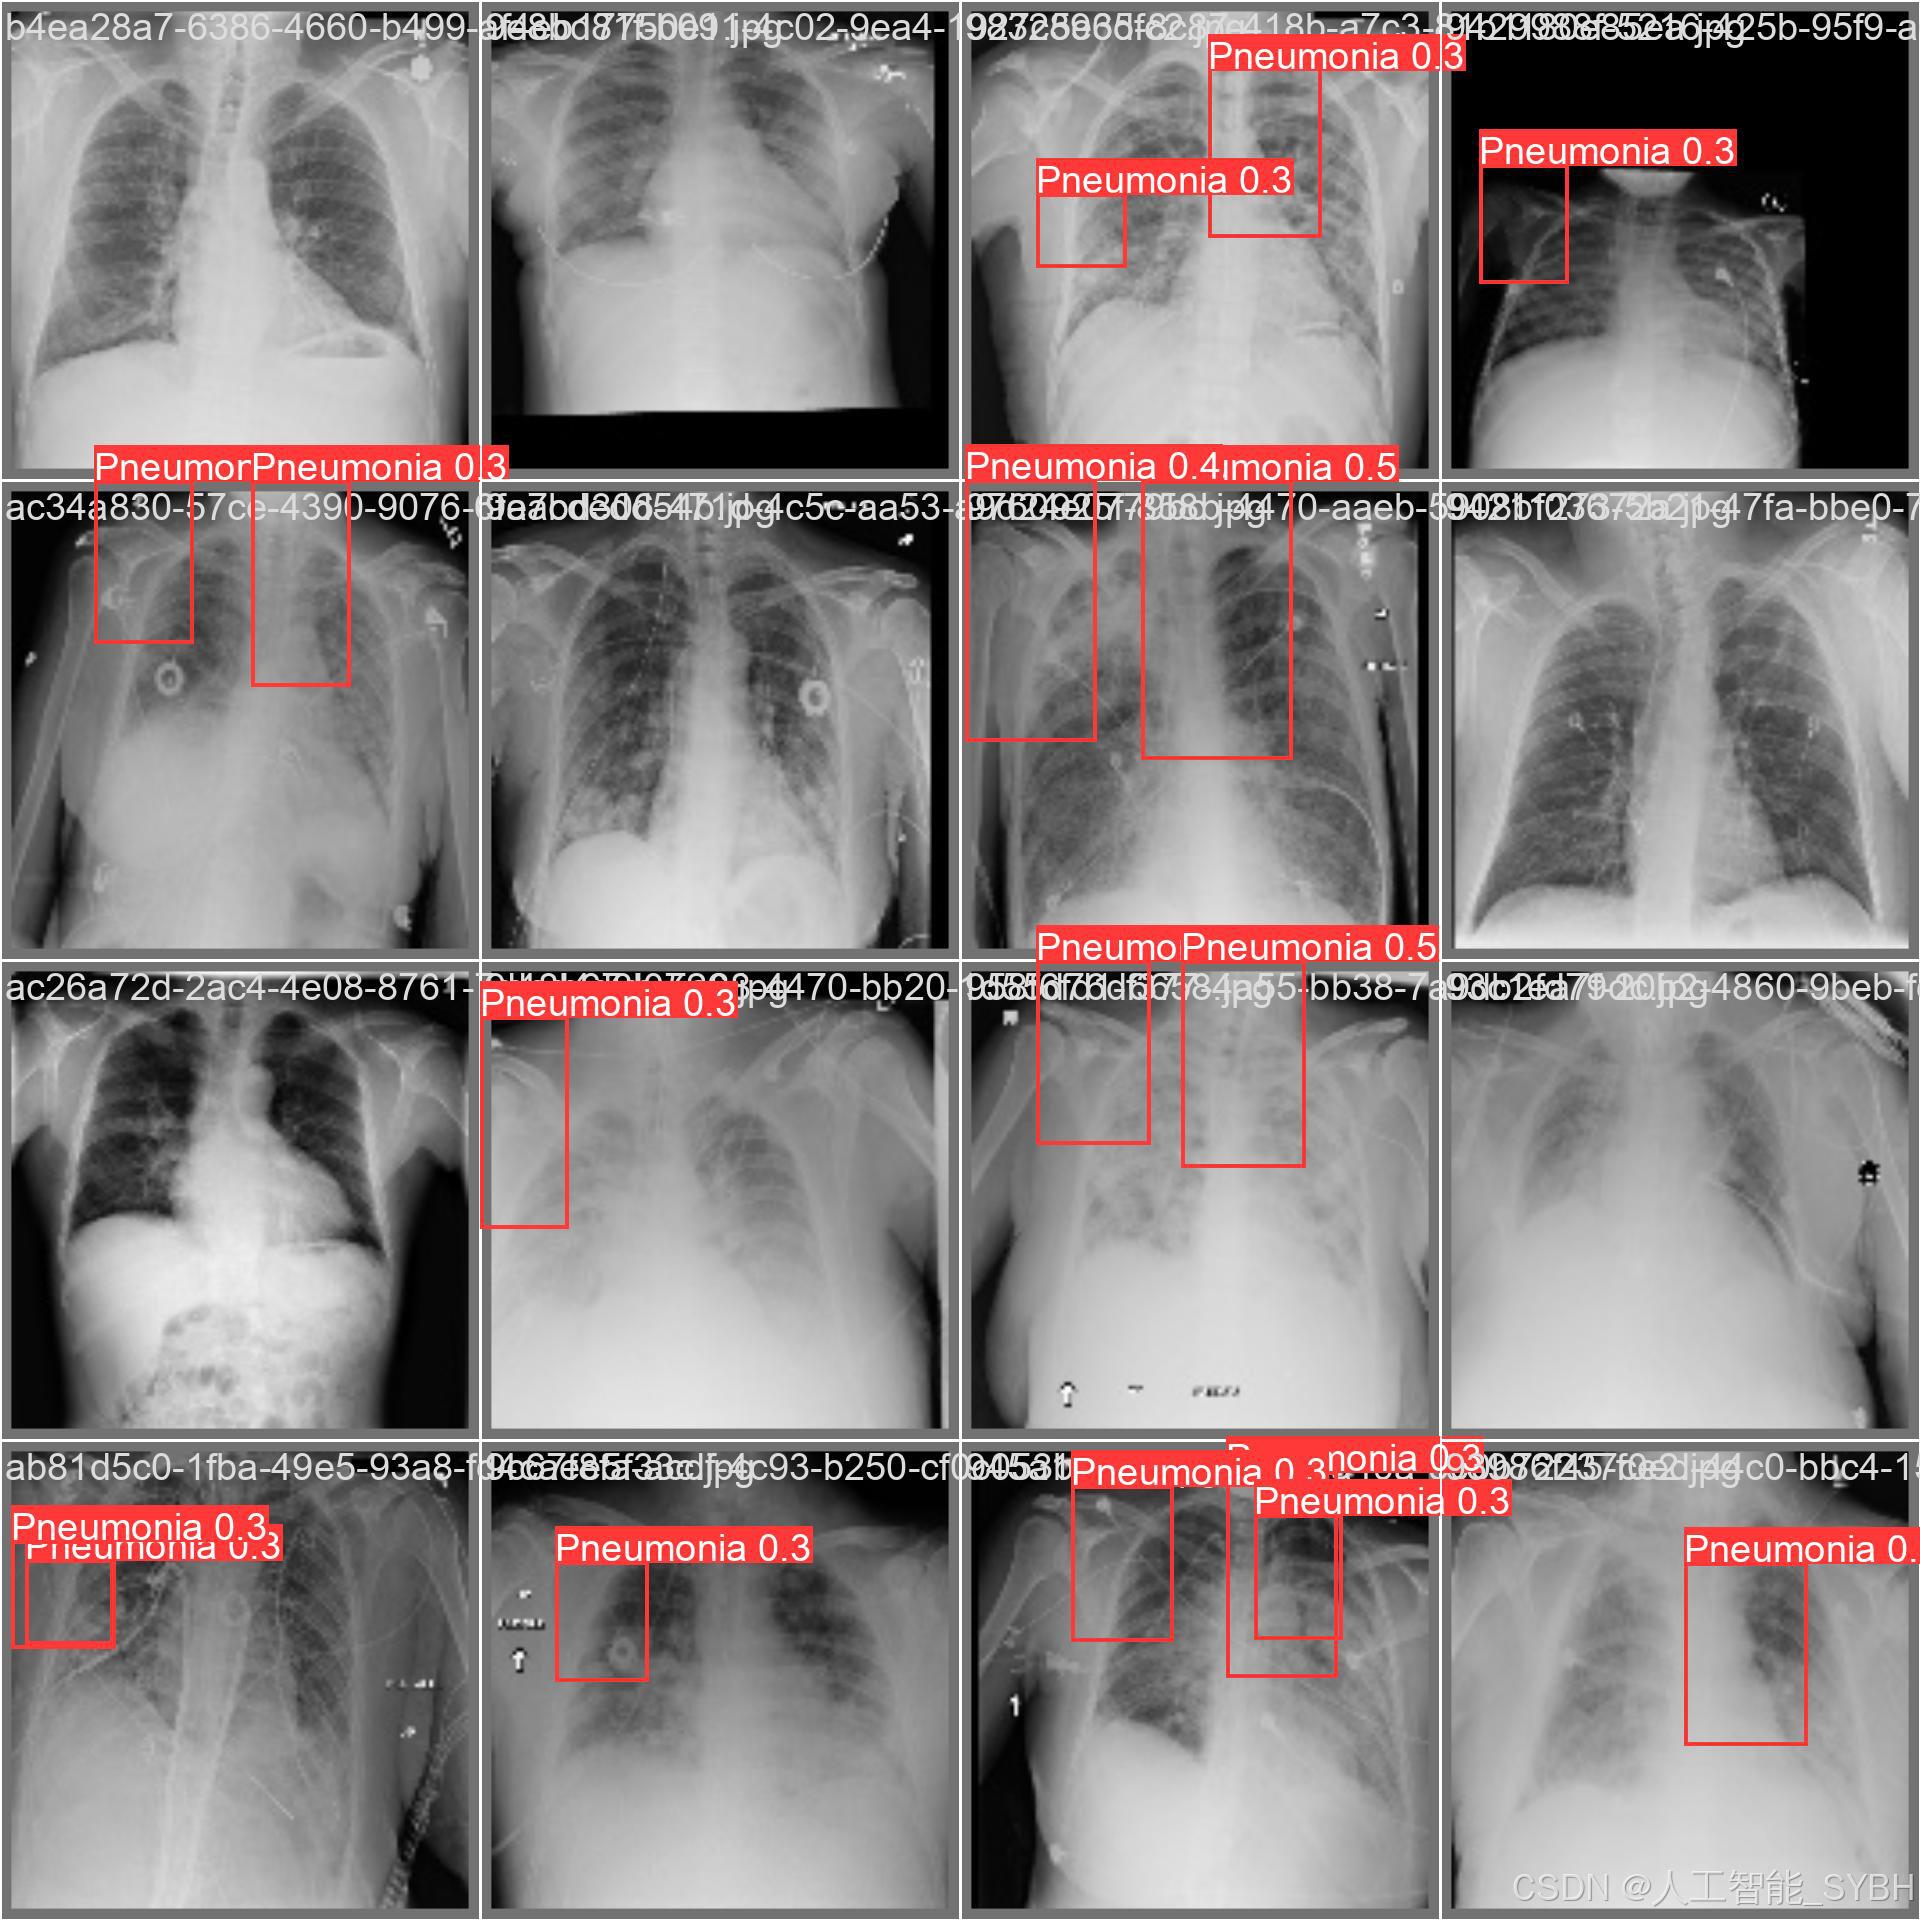

本项目基于YOLOv8深度学习框架,开发了一套高效、准确的肺炎智能检测系统,用于医学影像(如X光或CT扫描)中的肺炎识别。系统针对单类别('Pneumonia'肺炎)进行优化,采用包含3,772张训练图像、539张验证图像和1,078张测试图像的数据集进行训练和评估。该系统能够快速、自动地识别肺炎病变,辅助医生进行诊断,提高医疗检测效率,减少漏诊和误诊风险。

本项目基于YOLOv8深度学习框架,开发了一套高效、准确的肺炎智能检测系统,用于医学影像(如X光或CT扫描)中的肺炎识别。系统针对单类别('Pneumonia'肺炎)进行优化,采用包含3,772张训练图像、539张验证图像和1,078张测试图像的数据集进行训练和评估。该系统能够快速、自动地识别肺炎病变,辅助医生进行诊断,提高医疗检测效率,减少漏诊和误诊风险。

本系统利用计算机视觉和深度学习技术,实现了对肺炎影像的高精度检测,适用于临床辅助诊断、远程医疗筛查和大规模流行病监测等场景。相比传统人工阅片方式,该系统能够大幅缩短诊断时间,提高检测一致性,并降低医疗资源消耗,具有重要的临床应用价值。

✅ 图片检测:可对单张图片进行检测,返回检测框及类别信息。

✅ 批量图片检测:支持文件夹输入,一次性检测多张图片,生成批量检测结果。

图片检测

该功能允许用户通过单张图片进行目标检测。输入一张图片后,YOLO模型会实时分析图像,识别出其中的目标,并在图像中框出检测到的目标,输出带有目标框的图像。批量图片检测

用户可以一次性上传多个图片进行批量处理。该功能支持对多个图像文件进行并行处理,并返回每张图像的目标检测结果,适用于需要大规模处理图像数据的应用场景。

训练结果